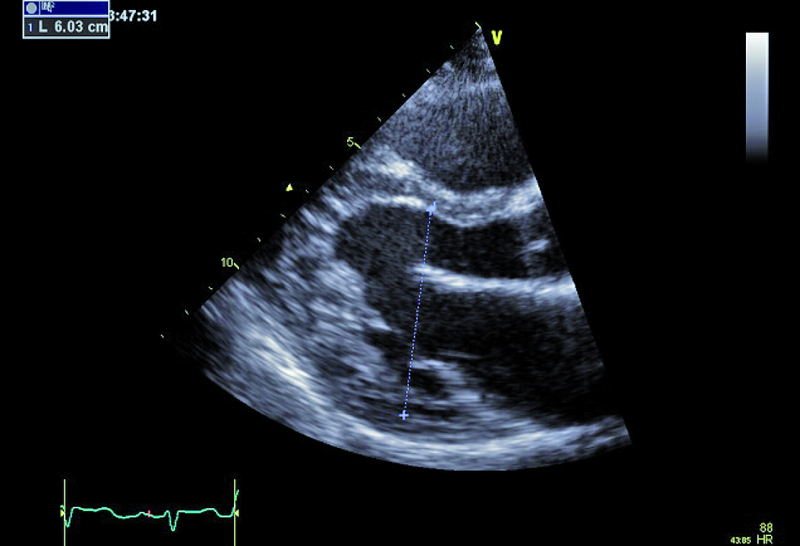

Kobieta, lat 36. Jakie patologie można rozpoznać na zamieszczonych rycinach?

1. Ubytek części błoniastej przegrody międzykomorowej (ryc. 1, 2).

2. Mały przeciek lewo-prawy przez przegrodę międzykomorową (ryc. 1, 2).

3. Nieznaczne powiększenie jamy lewej komory (ryc. 3).